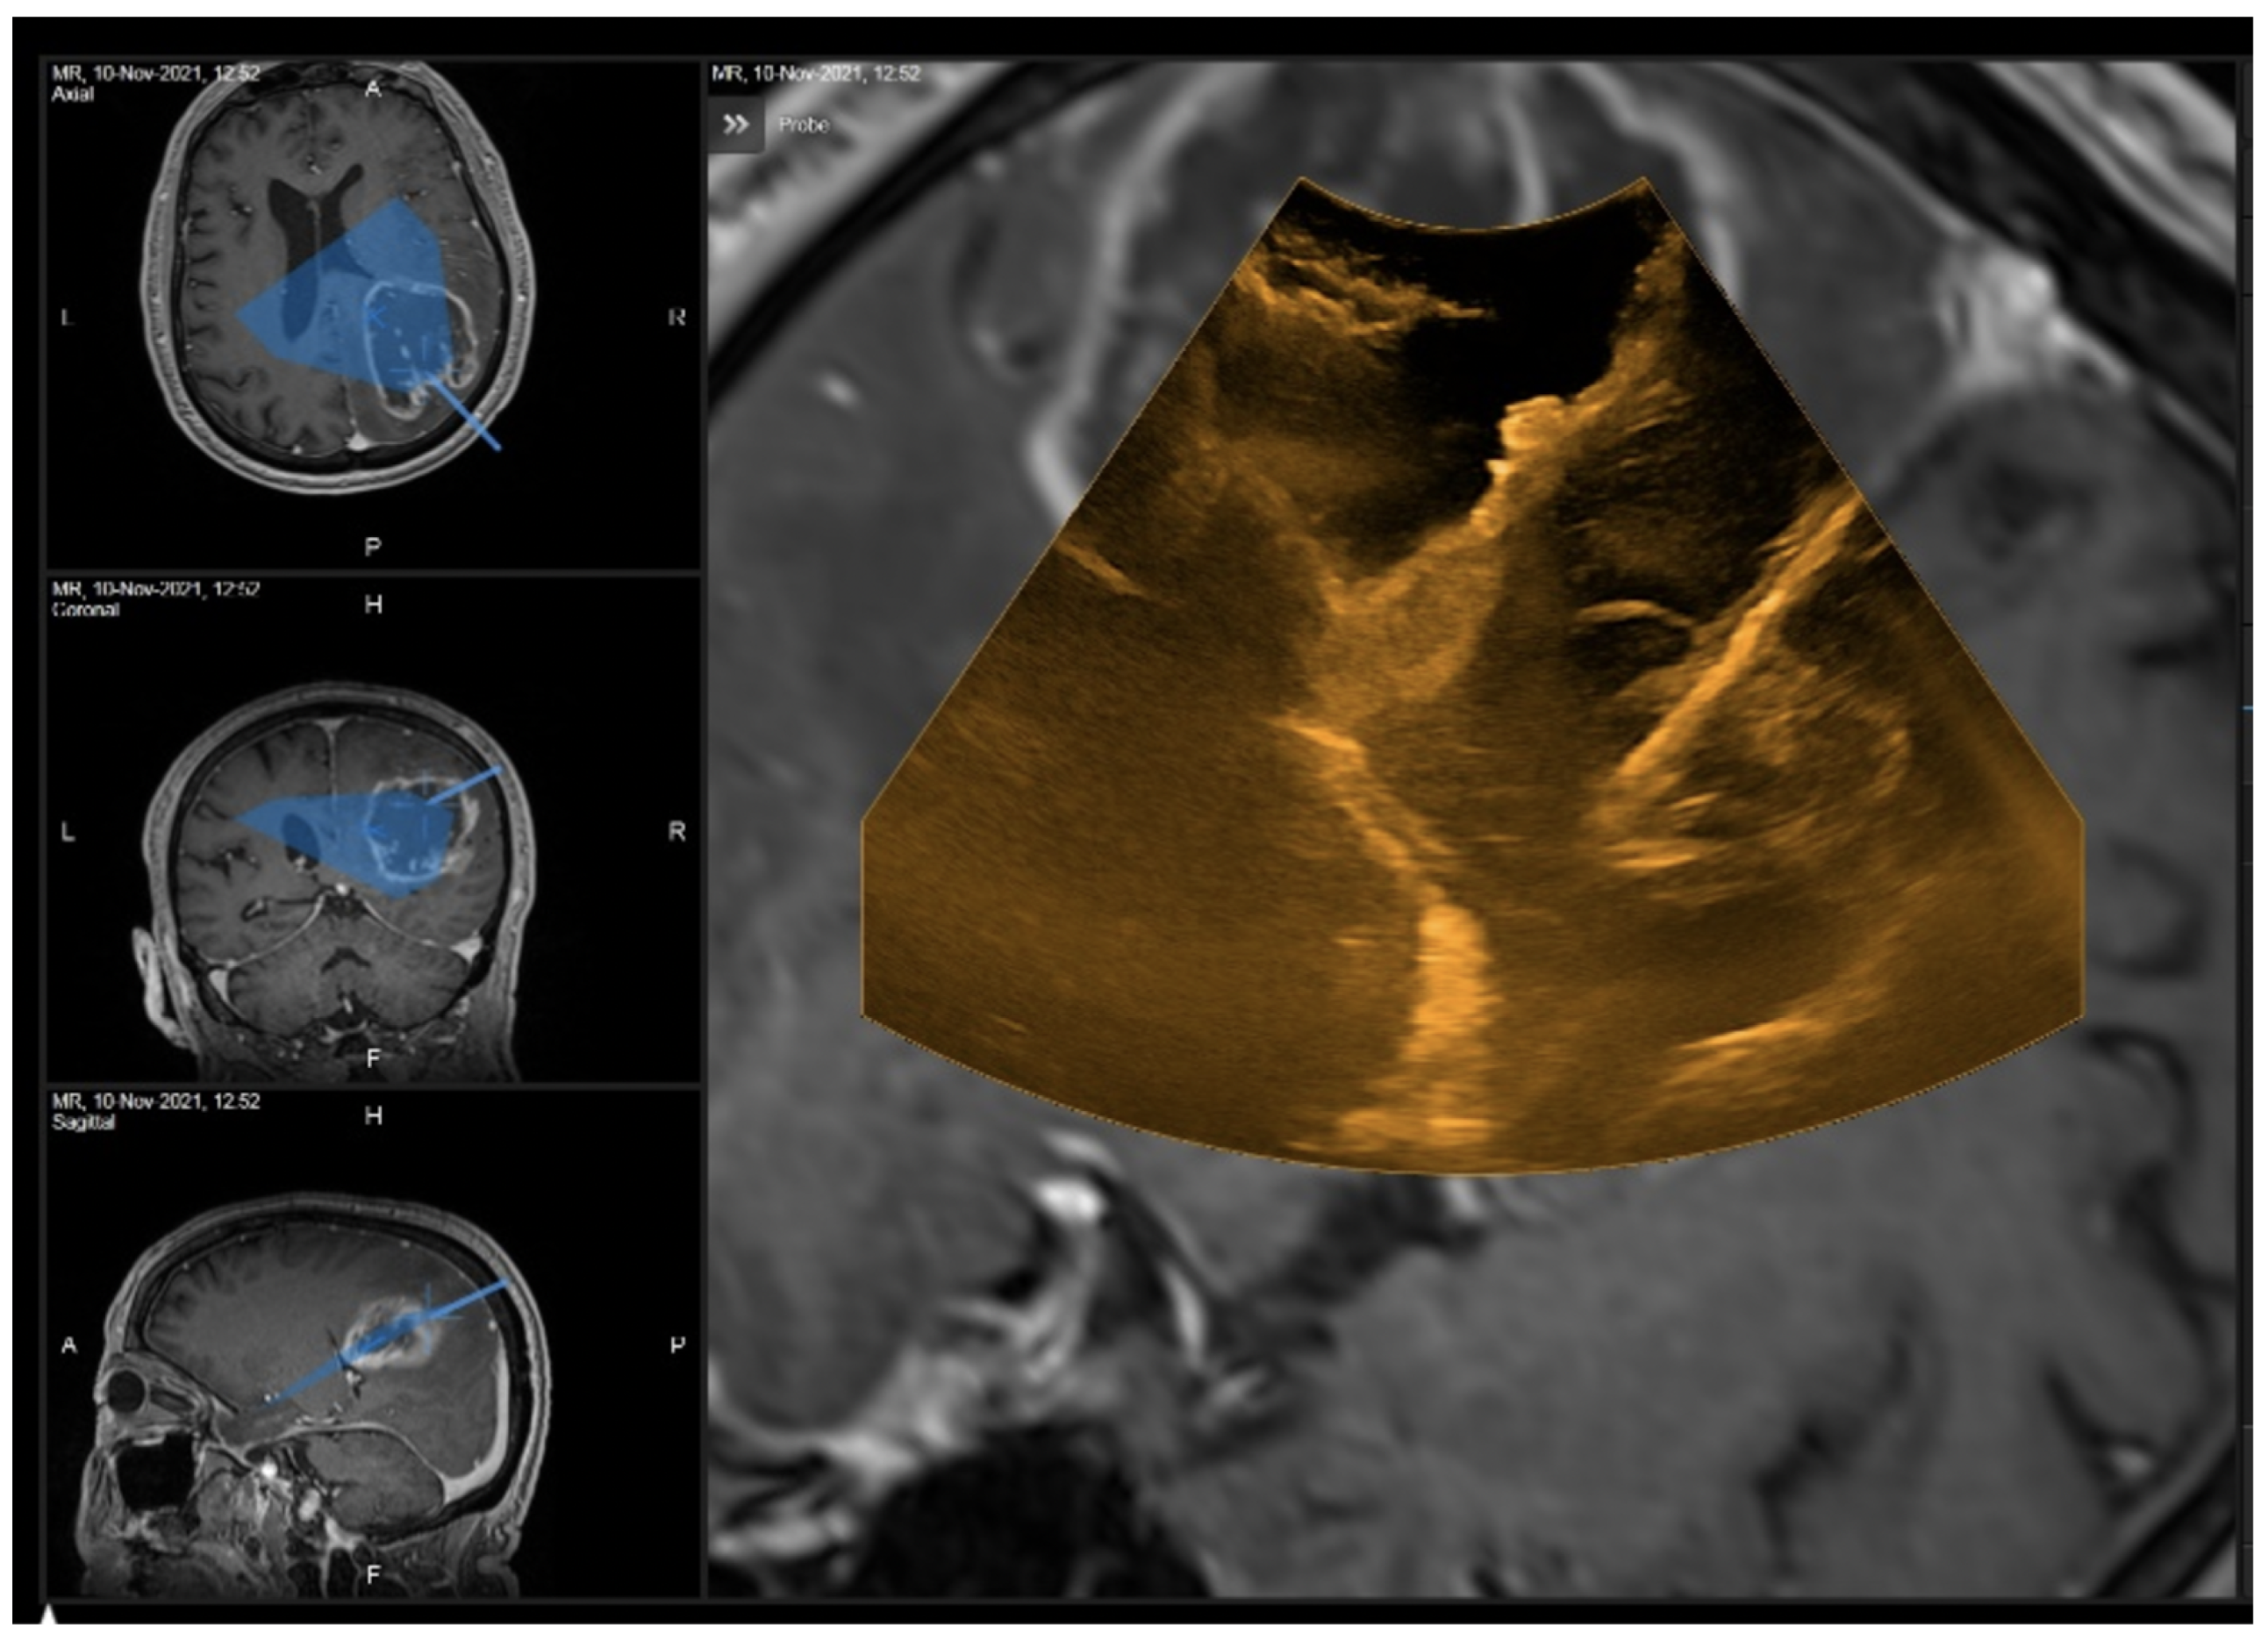

3.1.3. Case 3

4. Discussion